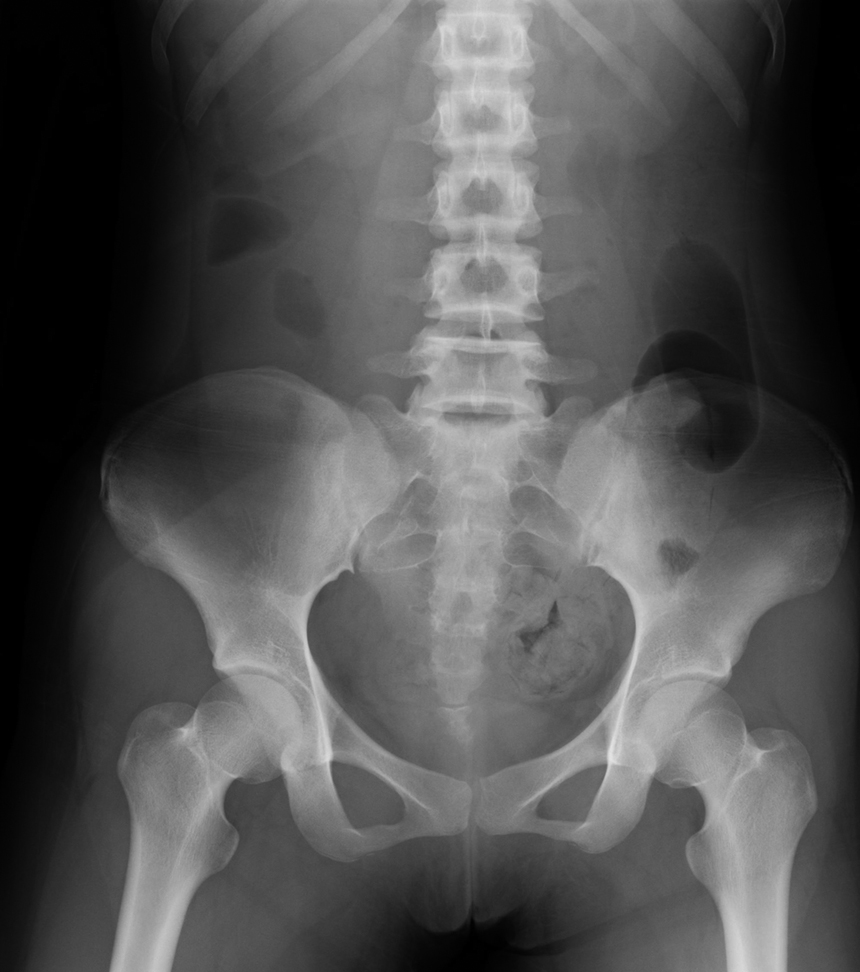

腹部単純X線写真所見:結腸にガスと便塊を認めた(Fig. 1).

Abdominal X-ray showed coprostasis in the sigmoid colon and gas in the descending colon.